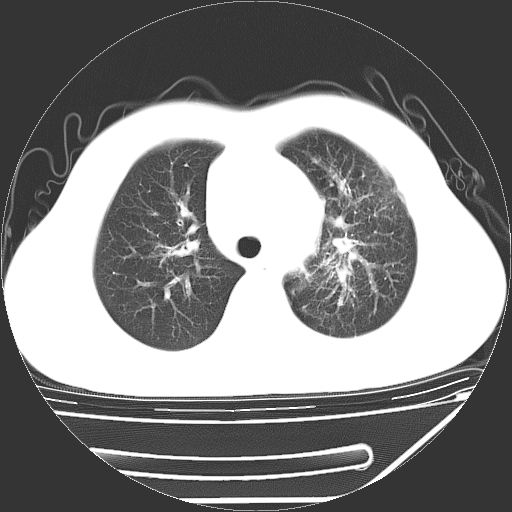

男,13岁,咳嗽、咳痰伴发热一周。

中上纵隔见多枚淋巴结肿大,部分相互融合成团片,左肺门增大,上叶支气管变窄,肺内多处斑片状 索条状及棉絮状致密影。临床“男,13岁,咳嗽、咳痰伴发热一周。”首先考虑:原发综合征!不除外淋巴瘤可能!

纵隔多发肿大淋巴结,部份有融合改变。双肺血管气管束增厚,以肺门为中心向外周散发,以左肺下叶为明显。考虑淋巴瘤可能性大。不除外原发综合征。

中上纵隔见多枚淋巴结肿大,部分相互融合成团片,左肺门增大,上叶支气管变窄,左肺支气管血管束增粗,可见磨玻璃样影。临床“男,13岁,咳嗽、咳痰伴发热一周。”首先考虑:淋巴瘤可能性大!

左肺野见淡片状影,病因整体多考虑结核

单纯看片子感觉左侧肺通气不畅,而不像肺内病变引起的纵隔病变。而且纵隔及左肺门都有淋巴结增大。首先还是考虑一下结节病,不排除淋巴瘤!!!